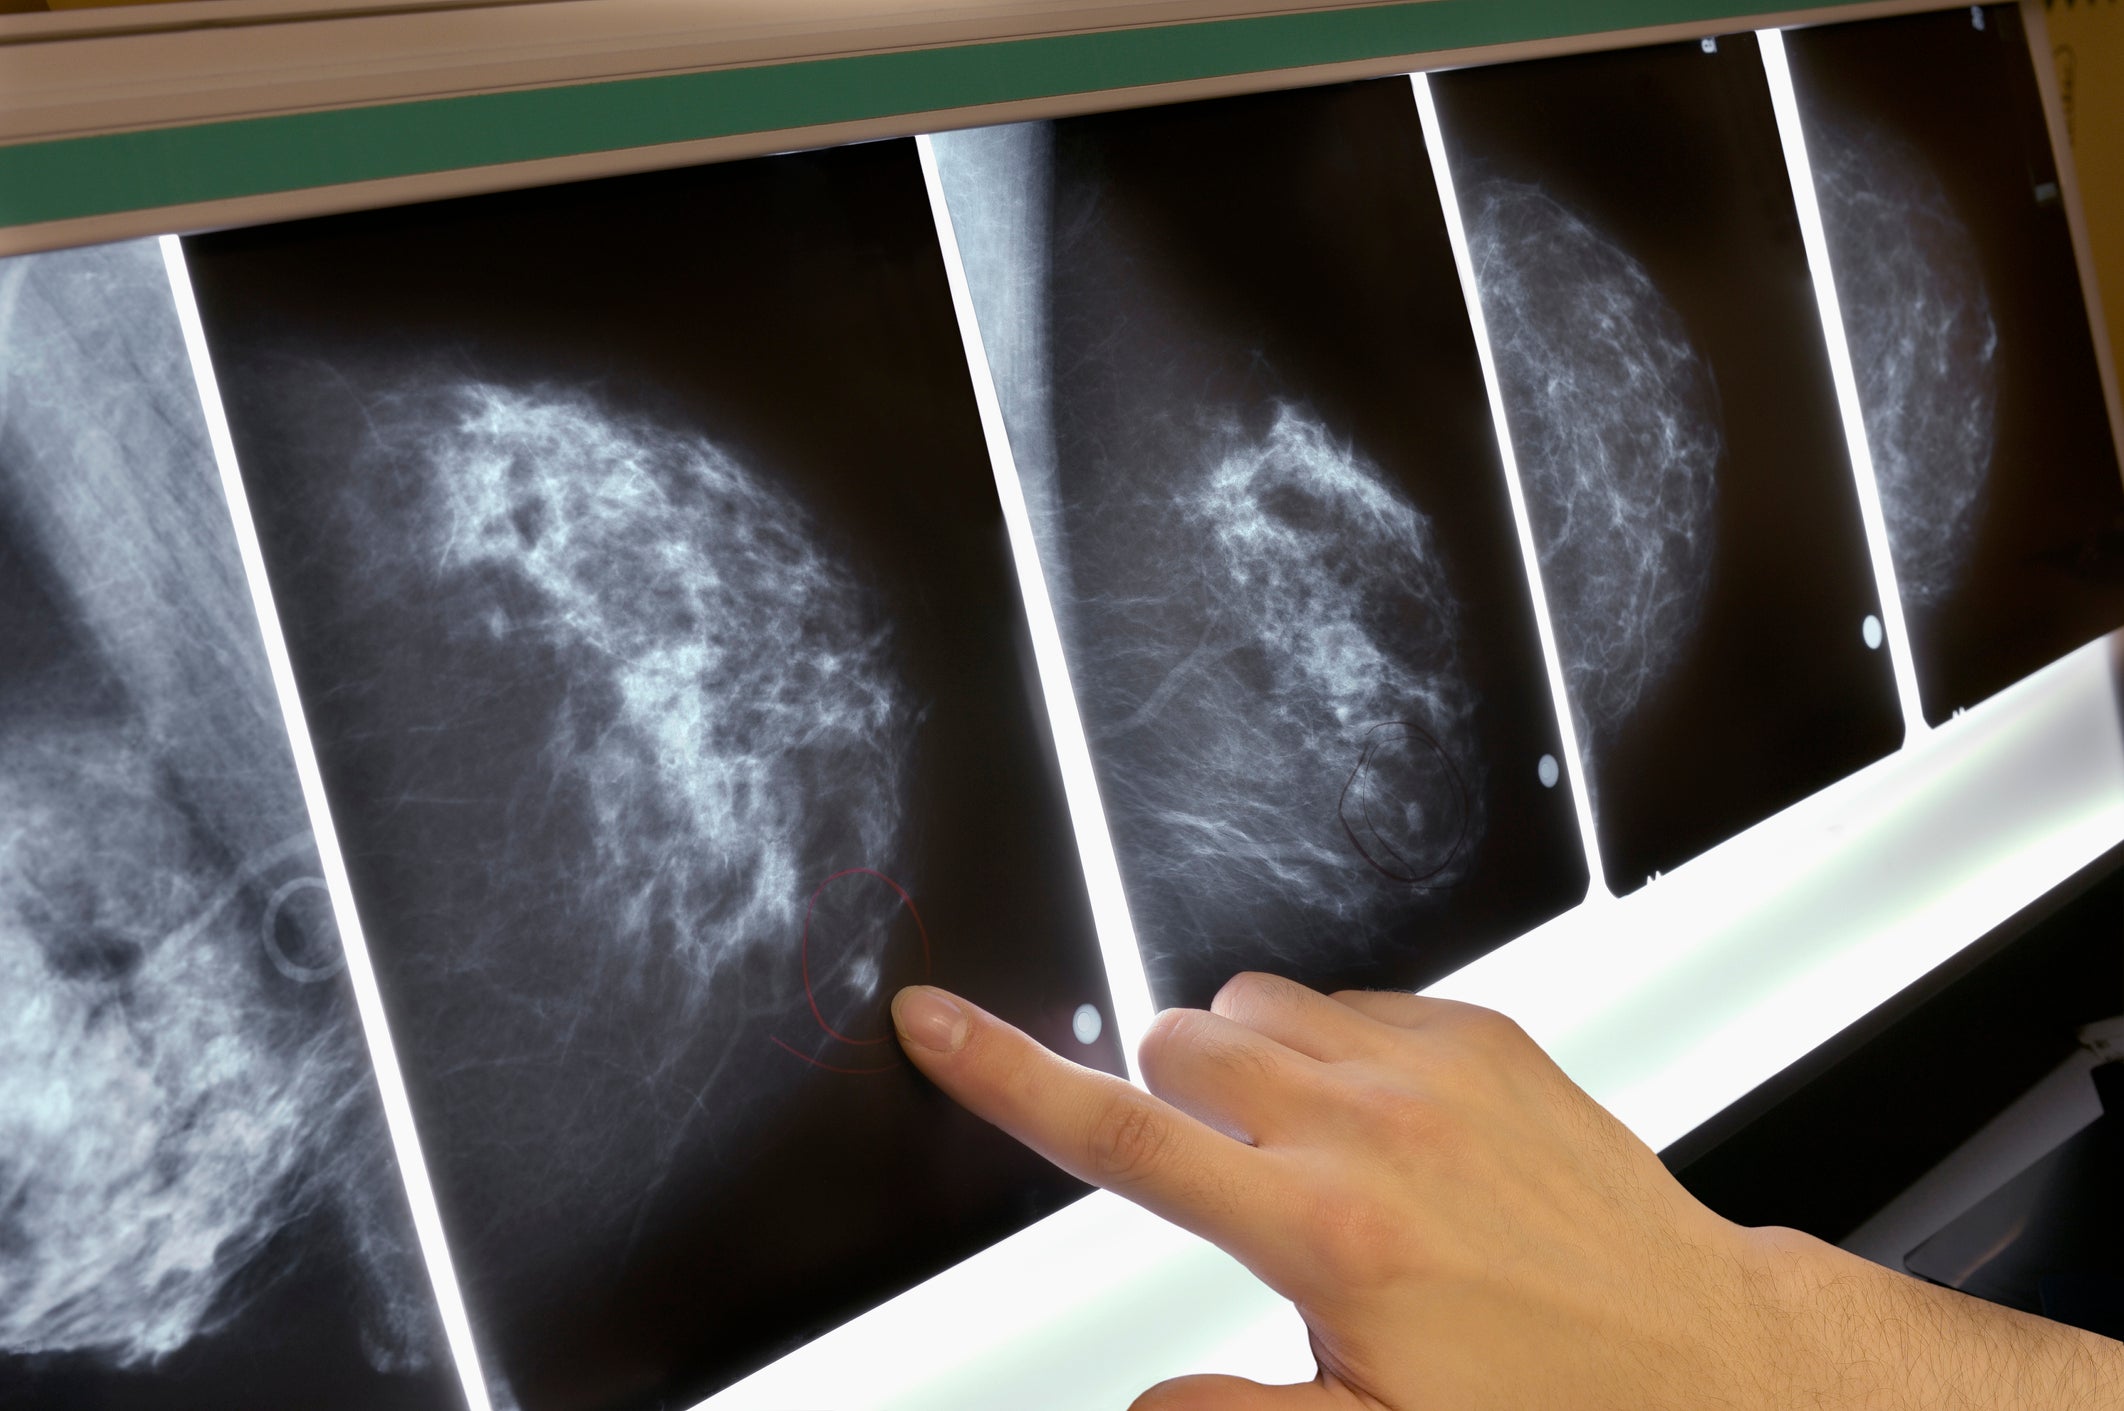

Risk Factors Associated With Breast Cancer That You Can Change from cdn-ajkoo.nitrocdn.com Mammograms can spot breast cancer before you can feel lumps in your breast. The study found while the risks of breast cancer gradually decreased after women stop using hormone therapy, some increased risk the use of mht rapidly increased during the 1990s, before the publication of. Menopause is complex and every woman experiences it differently so we xv stachenfeld n. Like many conditions, risk factors for breast cancer fall into the categories of things you can control and these include getting your period before age 12, entering menopause after age 55, having no children, or. Terms in this set (12). However, when the symptoms of these disorders disappear, the addiction remains and it can be very difficult to shake the. Hormonal changes during menopause and the impact on fluid regulation. What breast cancer treatments can cause menopausal symptoms?

Breast Cancer Symptoms Stages Types And More from post.healthline.com Of course they get breast cancer. Menopause is complex and every woman experiences it differently so we xv stachenfeld n. Current treatment options, challenges and future directions. Read more about the symptoms, causes and treatments. Breast cancer happens when cells in the breast grow and divide in an uncontrolled way. Kotsopoulos wonders out loud, maybe breast cancer worry has meant millions of women suffered menopause symptoms needlessly. Mammograms can spot breast cancer before you can feel lumps in your breast. Ama does not balance the estrogen with the personalized amount of progesterone for your body and maintain that correct balance through regular.

Breast Cancer Risk From Using Hrt Is Twice What Was Thought Cancer Research The Guardian from i.guim.co.uk Getting screening tests regularly may find breast, cervical, and colorectal (colon) cancers early, when treatment is likely to work best. A major cause of postmenopausal cancer is smoking. Menopause is complex and every woman experiences it differently so we xv stachenfeld n. Mammograms can spot breast cancer before you can feel lumps in your breast. Why do i get hot flushes? Sulforaphane, a dietary component of broccoli/broccoli sprouts, inhibits breast cancer stem cells. It is the varied symptoms that affect her life before, during, and even after menopause. Hrt can raise breast cancer risk from an estimated 6.3 per cent to 8.3 per cent.